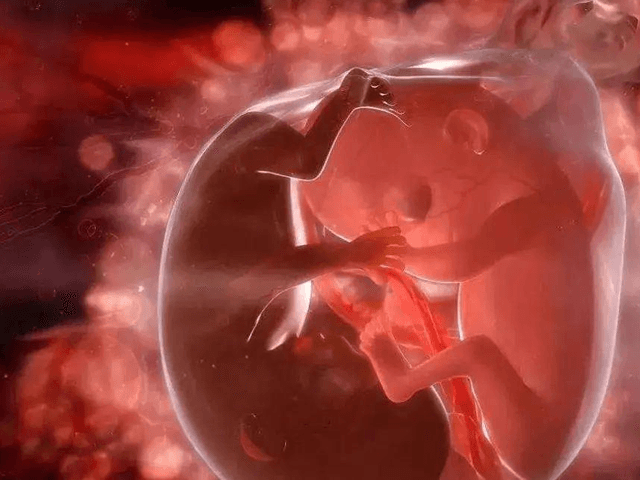

孕周越大胎盘植入的严重性确实可能会更严重,这种疾病是孕期比较严重的一个并发症,如果发生该病有可能会随着孕周增加,胎盘植入的深度也会增加,还有可能会波及到宫腔以外的部位。孕周越大胎盘植入越深的条件不过孕周越大胎盘植入越深有一定条件,第一个条件是前置胎盘,第二个是子宫有损伤,只有完全符合条件时才会出现这种情况,就是具体的原因介绍:一般情况下女性胎盘只是贴在子宫表面,随着孕周增大,胎盘面积虽然逐渐增大,...